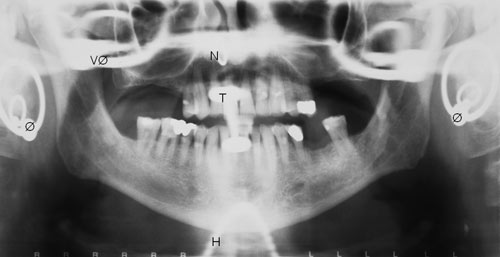

Panoramaradiografi er en røntgenteknik baseret på tomografi (snitfotografering), som resulterer i et billede af en patients underansigt. Et sådant billede benævnes et panoramabillede og skal i en standard version gengive patientens kæber i deres helhed. I praksis betyder det gengivelse af alle anatomiske strukturer fra øre til øre i horisontal retning og fra hagespids til bunden af øjenhulerne i vertikal retning (Fig. 1).

Fig. 1. Standard panoramabillede (horisontale pile markerer øreåbningerne, vertikale hvide pile markerer underkæbens nedre begrænsning og vertikale sorte pile markerer bunden af øjenhulerne).